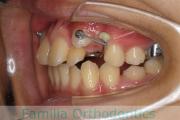

犬歯が八の字になっているので何とかしてほしいということで来院されました。上顎犬歯が左右とも前歯の方に向いていて、一期治療でまずは萌出誘導を行いました。

二期治療は、出っ歯の要素が強かったため、上顎のみ第二小臼歯を抜歯しています。

二期治療は2年強、25回程度の通院が必要でした。犬歯の埋伏歯は、うまく出すことができない場合があったり、出す際に周囲の歯の歯根に傷をつけるリスクがあったりします。